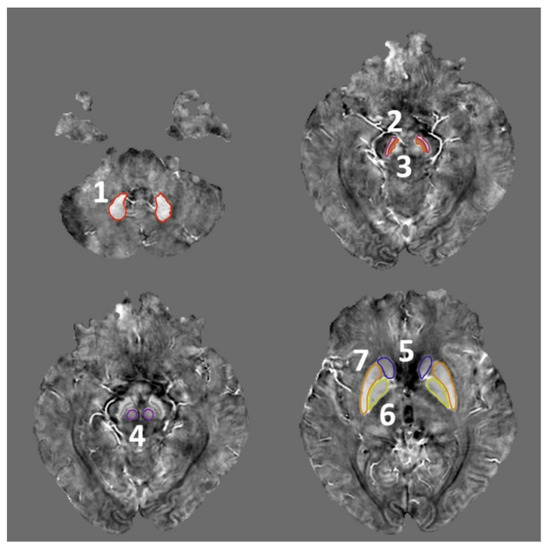

2.4. ROI Selection